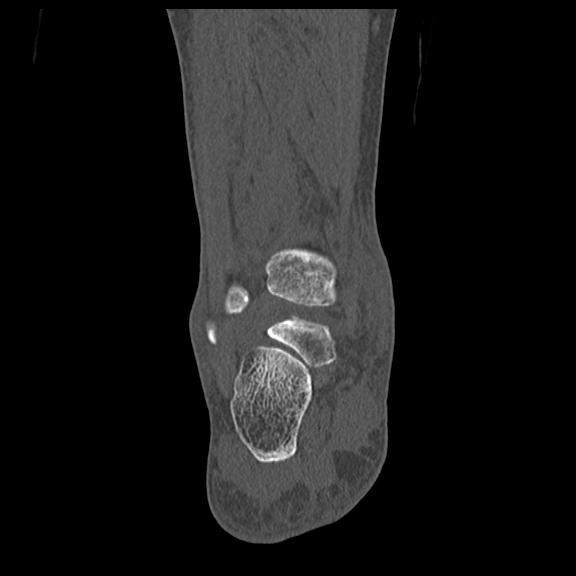

102755 1/4 2R 1/15 2R 右足関節 68歳女性 右三果脱臼骨折